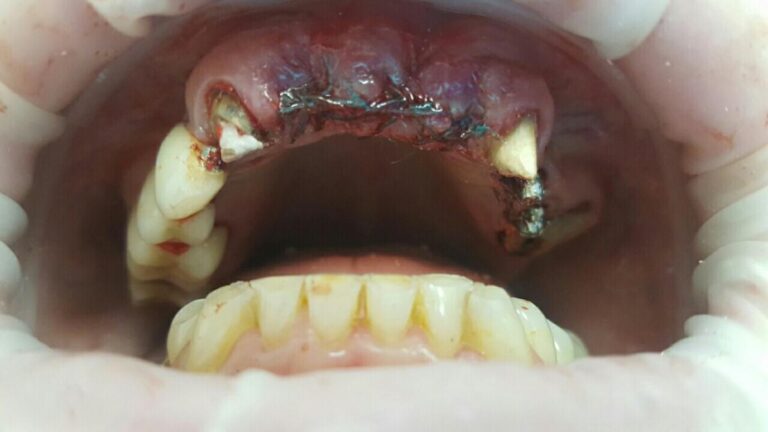

A patient case to the dental clinic with complaint connected with frond teeth defects. After the examination, he decided to provide dental treatment that includes immediate implantation of Alpha Dent implants. During the surgery he has placed 3 Alpha Dent implants in extracted teeth alveolar sockets. Then he placed allomaterial for bone regeneration over implants and sutured the wound.